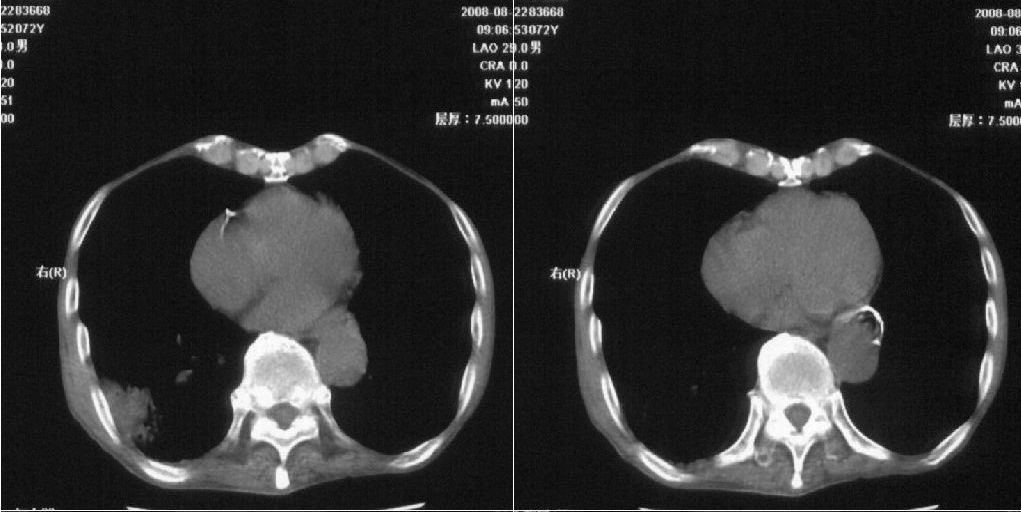

标题: CT15789:男性,72岁。食管癌术后14年。 [打印本页]

标题: CT15789:男性,72岁。食管癌术后14年。

痰培养:见葡萄球菌,霉菌少量生长。(此片系外院所作,仅提供了增强后的ct值为100hu,中心的坏死部分无强化,患者现在身体状况欠佳,为恶液质状态)

该患者通过抗炎治疗明显好转:当时患者消瘦,实是因为患者进食量不多。患者有食道癌,因发生原发肺癌的机率并不高,当时的ct片除了增强感觉有强化外(其实这信息也并不确定,因为是外院ct),其实并没有发现支气管腔改变等直接征象。经过治疗,患者现在一般情况良好。以下是9月22日的复查片,发现病灶吸收明显。纵隔窗就不上传了。